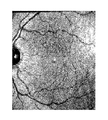

• FIG. 1A is an original retina fundus image showing the vasculature of a healthy volunteer.

• Examples of retinal phantoms captured using an embodiment of the present invention is represented in FIG. 1 .

FIG. 1A is an original retina fundus image showing the vasculature of a healthy volunteer.

FIG. 1B is a filtered version of the retina image of FIG. 1A showing the vasculature of a healthy volunteer.

FIG. 1C is a realized phantom of FIG. 1A on an absorbing and scattering epoxy layer (divisions on the right hand side are in mm).

An example of using the laser speckle imaging system to capture retinal images is described in FIGS. 2 and 5. Examples of retinal phantoms captured using an embodiment of the present invention is represented in FIG. 1.

A laser speckle imaging system was constructed to measure the temperature of retinal phantoms, as shown in FIG. 1. The system can be seen in the image of FIG. 2. The system included a 12-bit, monochrome camera (Pantera® TF 1M60, Dalsa, Ontario, Canada) with 1024×1024 resolution, and maximum frame rate of 60 Hz. A 50 mm focal length F#1.3 lens (Precise Optics, Bay Shore N.Y.) was used with the camera for magnification and to obtain resolutions of up to 7 μm/pixel. The light source was a 640 nm, 200 mW diode laser (Melles Griot, Longmont, Colo.), connected to a single mode fiber.